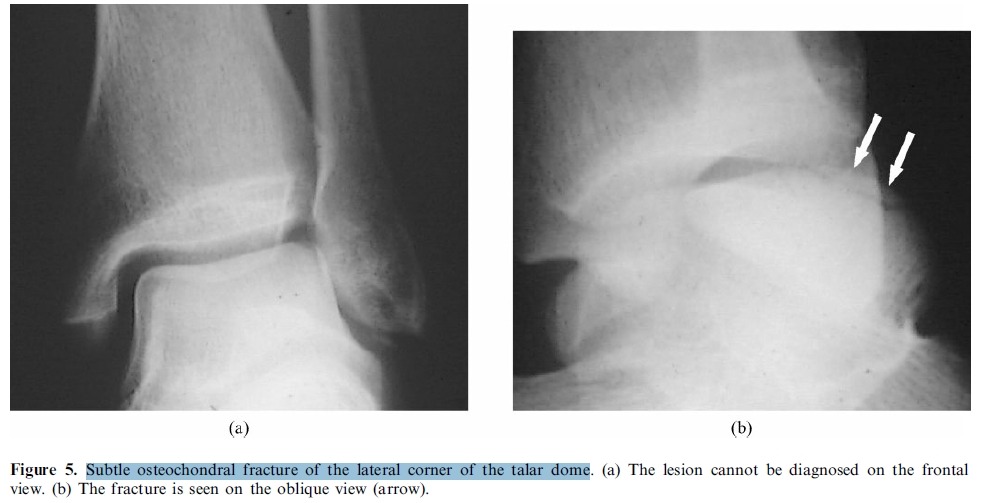

Subtle osteochondral fracture of the lateral corner of the talar dome